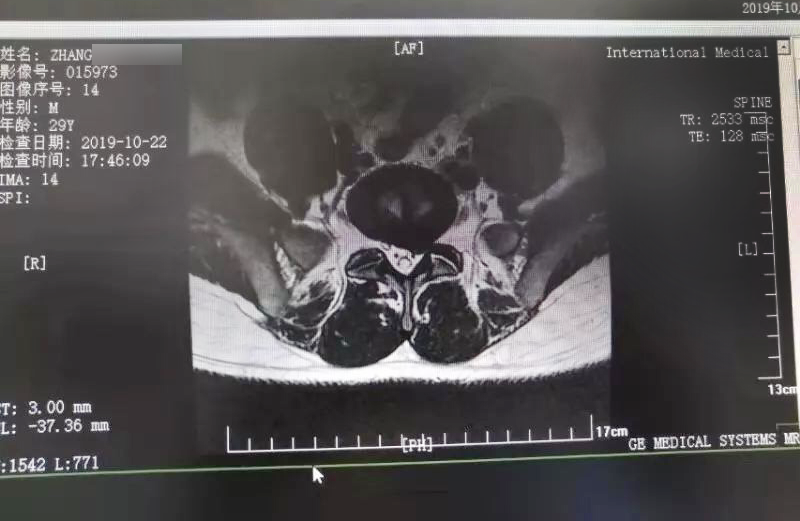

三秦都市報(bào)報(bào)道—女子腰腿痛兩年 醫(yī)生微創(chuàng)手術(shù)成功治療。點(diǎn)擊閱讀。

三秦網(wǎng)報(bào)道—西安國(guó)際醫(yī)學(xué)中心骨科醫(yī)院成功完成首例椎間孔鏡手術(shù)。點(diǎn)擊閱讀。